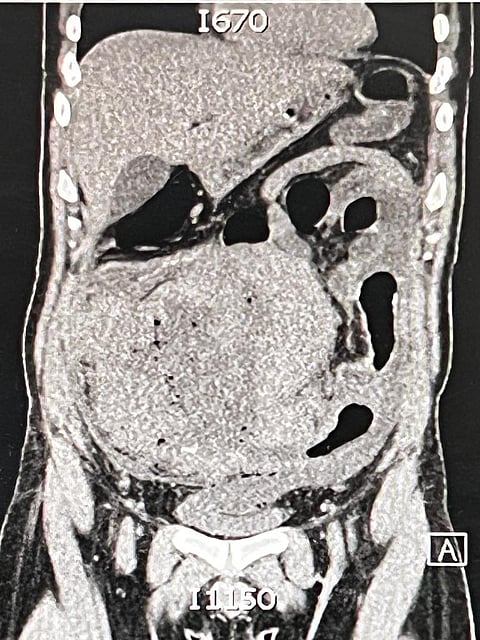

وفي التفاصيل أوضح لـ "سبق" سراج الحميدان ، متحدث صحة الطائف، أنه قد تم تنويم المريض ذي الـ 33 عامًا عن طريق الطوارئ، حيث كان يعاني آلامًا شديدة في البطن وأعراض صدمة إنتانية، وبعد إجراء الفحوص والأشعة اللازمة تبين وجود ورم مثقوب بالأمعاء بحجم 30*24*18سم، مما استدعى إجراء جراحة عاجلة من قِبل الفريق الطبي الجراحي.